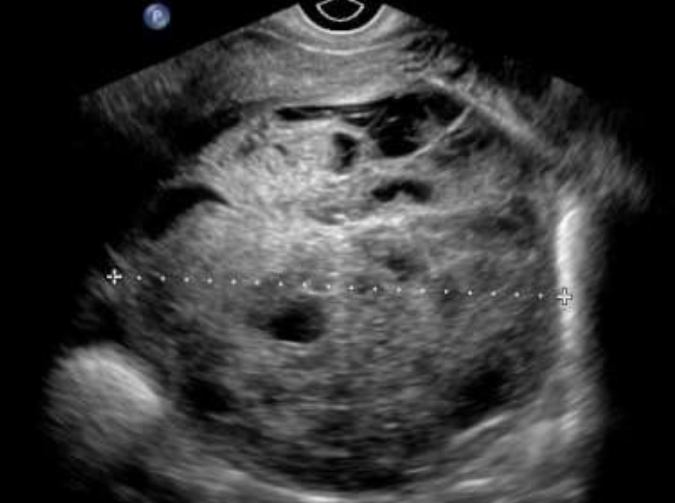

Det är relativt vanligt förekommande med metastaser i ovarierna från andra maligna tumörer, vanligast förekommande är metastaser från kolorektal, övre GI, ventrikel, lymfom och bröstcancer. Det finns studier som har visat att metastaser från lymfom, bröst-, och ventrikelcancer ofta är solida medan metastaser från colorektal, gallblåse, pancreascancer ofta är flerrummigasolida med inslag av nekros 10,11 (Bild 9-12). Vid spridd bukmalignitet kan vara svårt att tala skilja primär ovarialcancer från metastaserade cancer av annan genes, inslag av tumörnekros, avsaknad av ovarialtumör talar dock för icke ovariell genes. Transvaginal eller transabdominell mellanålsbiopsi är en snabb enkel minimal-invasiv metod att fastställa tumörens primaritet.

Bild 9. Coloncancermetastas hos 19 årig kvinna i HNPCC familj.